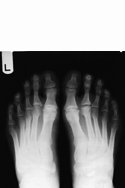

Koehler's disease was thought by many to be avascular necrosis of the tarsal navicular primarily based on the radiographic signs. It is now a much more controversial subject. Kohler's disease is can be a very confusing and ambiguous entity due to uncertain etiology and often times vague symptoms. A history of trauma is only elicited in approximately 35% of cases and symptoms that correlate with the radiographic signs are very sporadic.

When a diagnosis of Kohler's disease is made, the typical patient is a young male, typically between 3 and 7 years of age. It is unilateral approximately 75% of cases.

The controversy of Kohler's disease stems from the fact that many authorities feel that this process is not a "disease" at all, but rather a process of altered, but completely normal, ossification of the tarsal navicular which leads to the radiographic appearance.

There are two main reasons for the idea that this often times is not osteonecrosis is the fact that 1) there are a lack of symptoms and 2) it is a self-limiting condition.

The radiographic appearance is sclerosis, overall flattening and deformity of the navicular. But, again, it's the associated signs and symptoms, as described that must be present for a confident diagnosis. MRI or bone scan may help confirm the diagnosis, but because of its self-limiting nature, it most likely is not warranted.